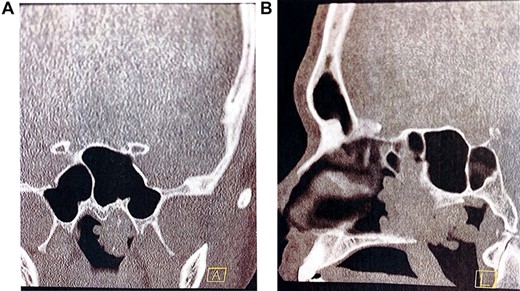

Pre-operative computed tomography of the nasal passage and sinuses. (A) Coronal CT sinuses (bone algorithm) demonstrating left nasopharyngeal space ‘polypoid’ type opacification, with evidence of intralesional calcification; (B) sagittal CT sinuses (bone algorithm) demonstrating a large polypoidal type opacification obstructing the posterior nasal choanae.

On examination, he had severely reduced left nasal airflow. Anterior rhinoscopy revealed a large fleshy tumour in the left nasal cavity, which was not papillomatous or vascular (Fig. 1). Nasendoscopic examination showed a large tumour of solid and polypoidal components. It occluded the posterior nasal choanae, filling the inferior aspect of the nose. Visualized from the right nostril, the tumour prolapsed into the postnasal space. There was no contact bleeding. The right nasal passage appeared normal. The nasopharyngeal vault and the remainder of the upper airway appeared normal. He did not have otitis media with effusion in the left ear and there was no palpable cervical lymphadenopathy. Pre-operative imaging was ordered to determine the extent of the lesion (Fig. 2).

Radiologically, the most common finding on a non-contrast-enhanced computed tomography (CT) sinus (bone algorithm) is opacification of sinuses whose ostea are blocked by a posterior nasal cavity polypoid lesion (namely, sphenoid and posterior ethmoid air cells) [1]. Vira et al. [8] retrospectively reviewed the perioperative CT scans of 35 patients with REAH and concluded that there were no distinguishing features that could differentiate it from any other sinonasal lesion. However, a later study found that a widened olfactory cleft, greater than 10 mm on CT imaging, is a characteristic feature of REAH [9]. The olfactory cleft is the distance between the both turbinal ethmoid walls and were significantly increased in patients with REAH in axial (12.2 mm) and coronal (12.1 mm) planes, when compared with patients with nasal polyposis (5.6 and 5.4 mm) and patients with no disease (4.5 and 4.2 mm) [10].